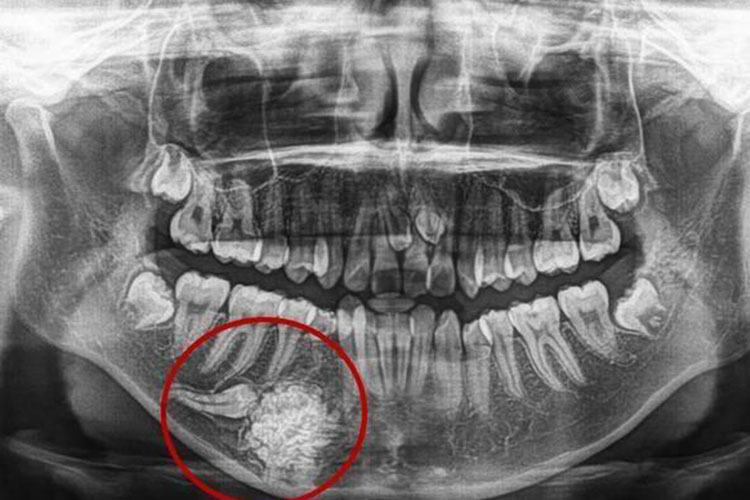

混合性牙瘤:早期发育期的混合性牙瘤,与成釉细胞纤维瘤或成釉细胞纤维一牙瘤不易区别,肿物生长有自限性。X线片表现为境界清楚的放射透光区,其中可见放射阻射性结节状钙化物,镜下见肿物内牙体组织成分排列素乱,相互混杂,而无典型的牙结构。多发生于儿童和青年,上下颌骨均可发生,以下颌前磨牙区和磨牙区多见。

组合性牙瘤:早期X线可显示形态及数目不一的牙样物堆积在一起,镜下见肿物由许多牙样结构所组成,这些牙样结构虽然不同于正常牙,但牙釉质、牙本质、牙骨质和牙髓的排列如同正常牙的排列方式,患者年较小,好发于上颌切牙-尖牙区。